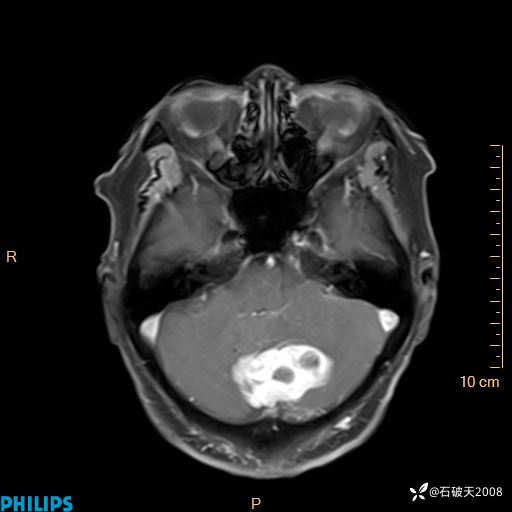

T2